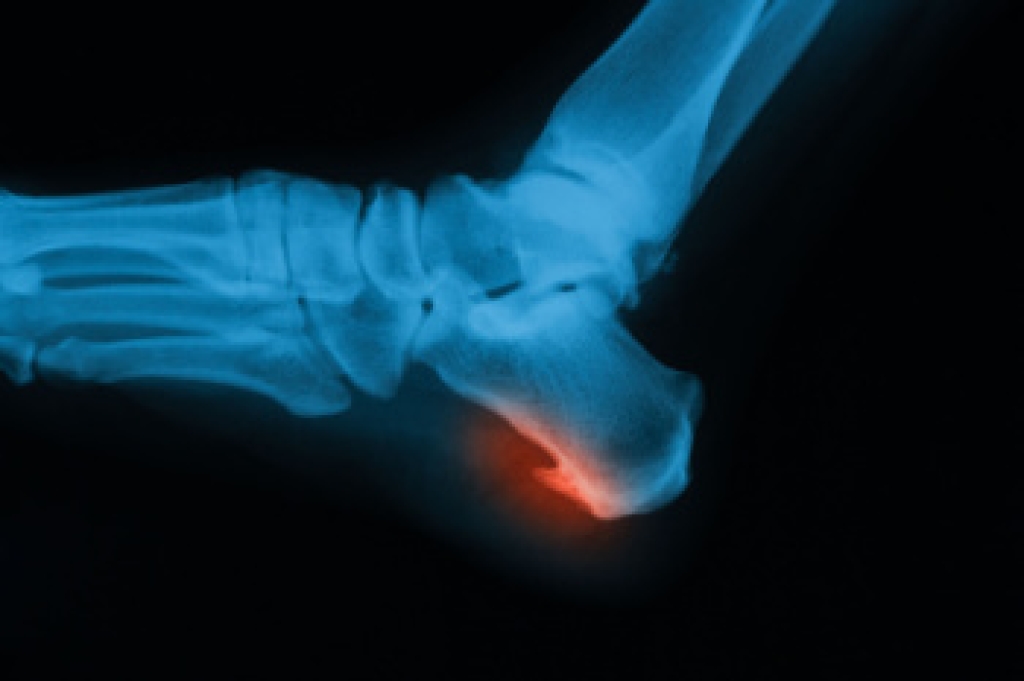

Pain in the arch of the foot can develop for several reasons, related to structure, strain, or injury. The arch is a curved area on the bottom of the foot that helps support body weight and absorb shock when walking. A frequent cause of pain in the arches is plantar fasciitis. This condition involves inflammation of a thick band of tissue that connects the heel to the toes. Flat feet or very high arches can also change how weight is distributed, placing extra stress on the arch. Overuse from prolonged standing, walking, or sports can strain muscles and ligaments. Injuries like sprains or small fractures may also lead to arch pain. A podiatrist can perform an exam and order imaging to confirm the cause. They also can provide orthotics, bracing, or suggested exercises to reduce strain and improve function. If you are experiencing foot arch pain, it is suggested that you make an appointment with a podiatrist for help.

To figure out the cause of foot pain, podiatrists utilize several different methods. This can range from simple visual inspections and sensation tests to X-rays and MRI scans. Prior medical history, family medical history, and any recent physical traumatic events will all be taken into consideration for a proper diagnosis.